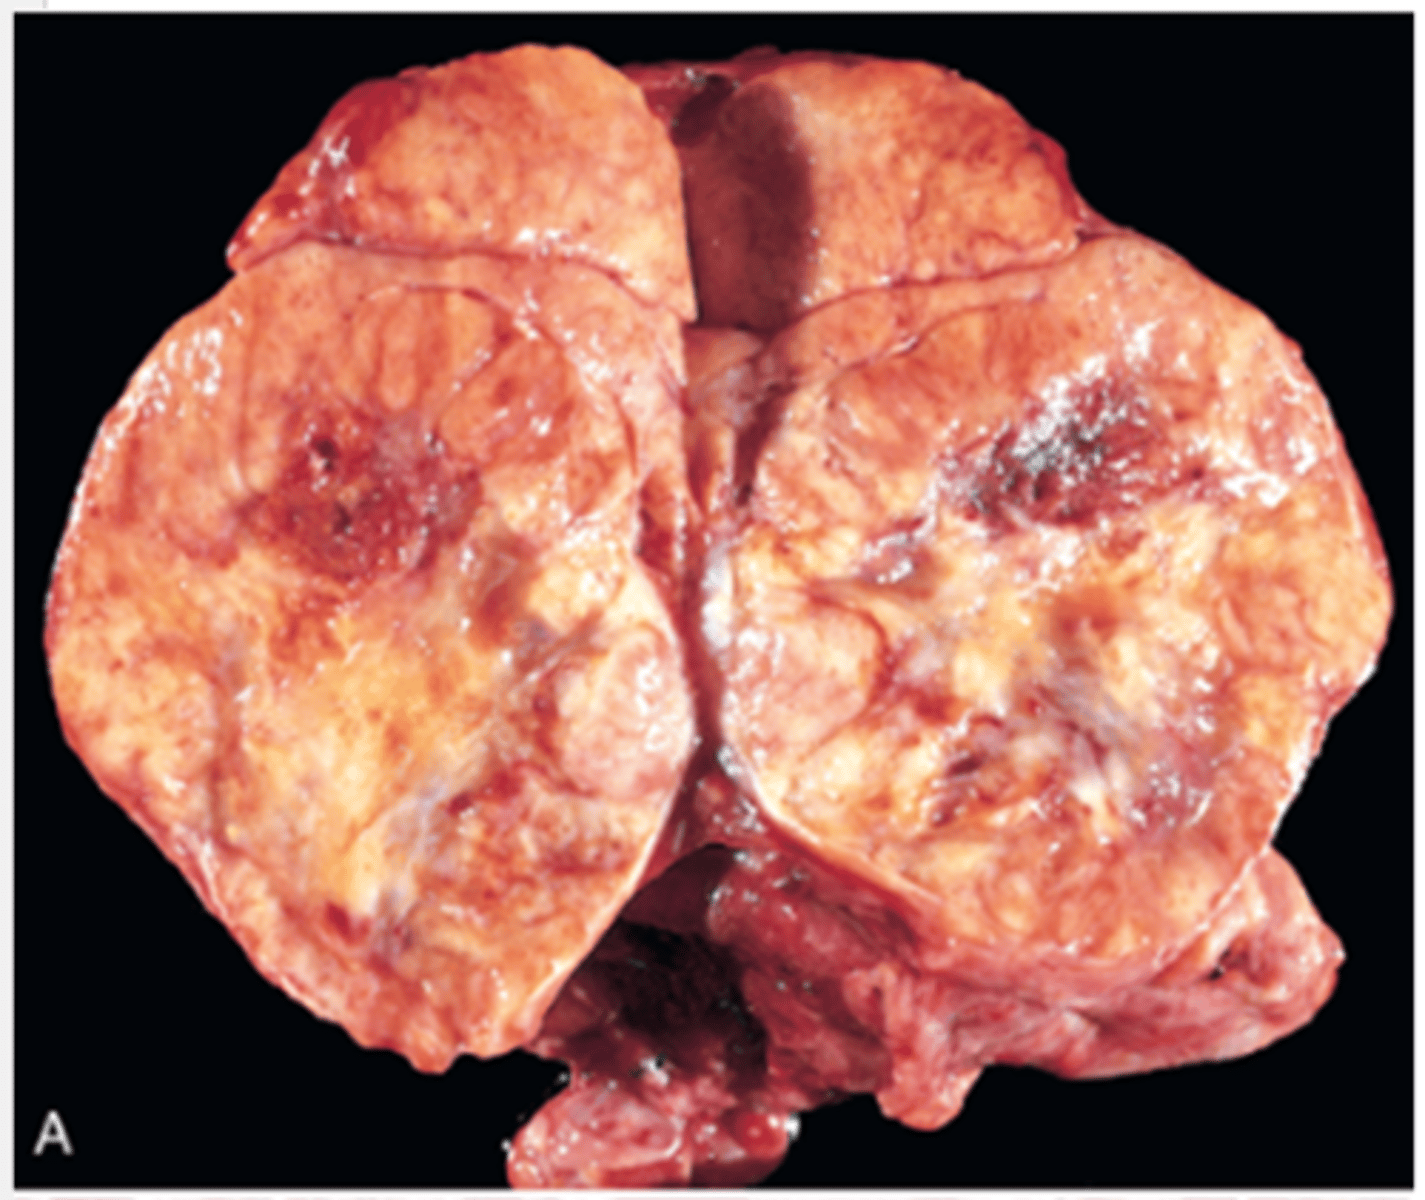

Adrenal Hyperplasia

Identify the pathology